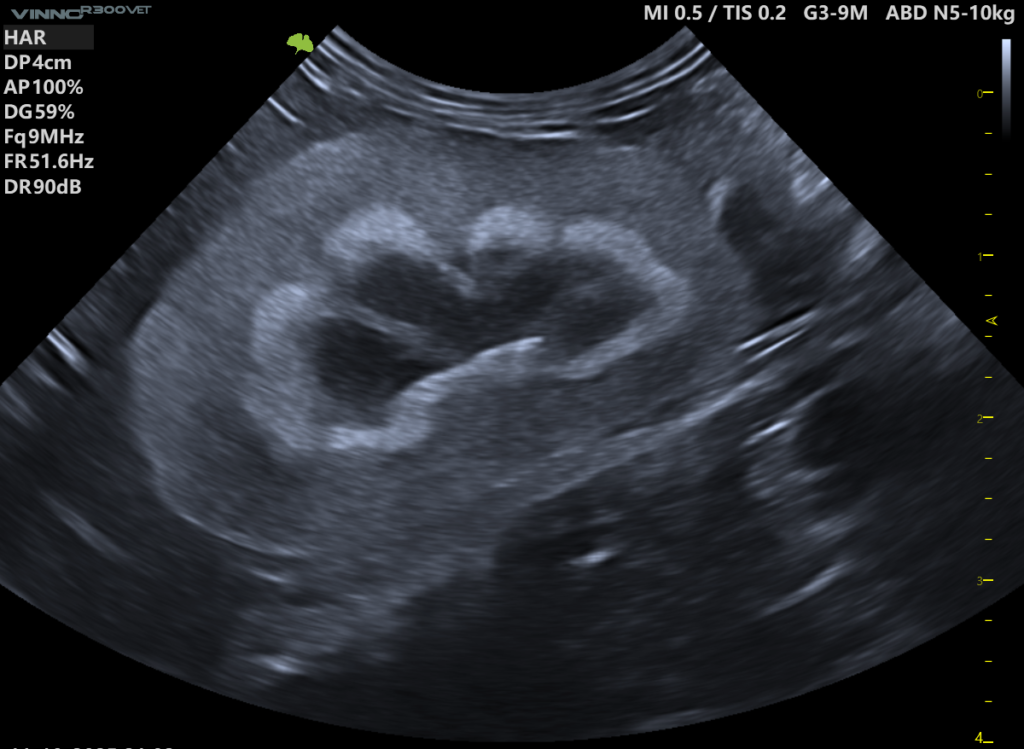

Medullary Rim Sign to hiperechogeniczna struktura w obrębie rdzenia nerki, przebiegająca równolegle do granicy korowo-rdzeniowej. Klasycznie opisywany jest jako cienka, jasna linia („rąbek”) oddzielająca korę od rdzenia.

Aktualnie proponowany jest podział MRS na dwa odrębne typy, różniące się potencjalnym znaczeniem klinicznym:

MRS-line (klasyczny objaw rąbka)

MRS-band / Medullary Band Sign (MRS-band) – objaw pasma rdzeniowego